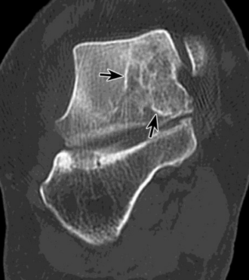

What is this? What is shown by A and B? | STJ coalition A = talar neck spurring B = Halo or 'C' sign |